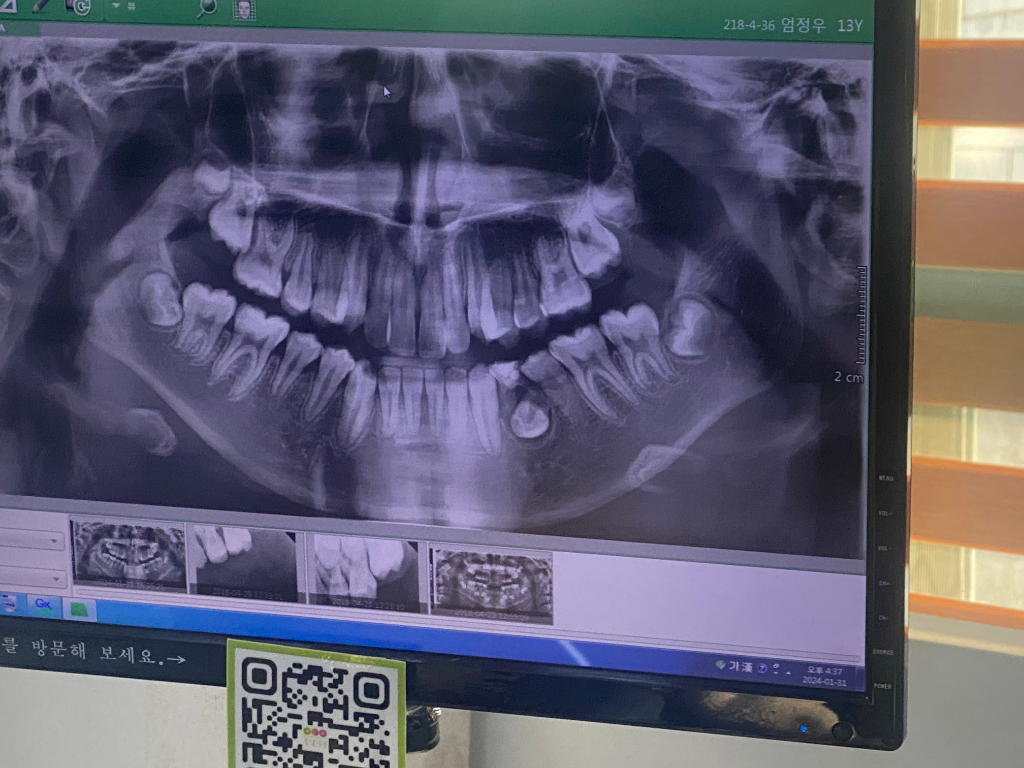

하지만 사진으로 봤을 경우에는 유치의 뿌리 쪽에 염증이 생겨서 고름이 차이는 것으로 보입니다.

이런 경우에는 유치를 발치를해주는 것이 좋으며 발치를 했을 때는 매복되어 있는 치아를 맹출 시키거나 보철 치료 등으로 치아가 없는 부위를 수복해 주는 것이 좋습니다.

다만, 사진상으로 확실하진 않으나 영구치 치관(치아머리) 주위가 낭포가 형성된 것이 맞다고 병리학적으로 판단되면 영구치도 사용하기 어려울 수도 있습니다.